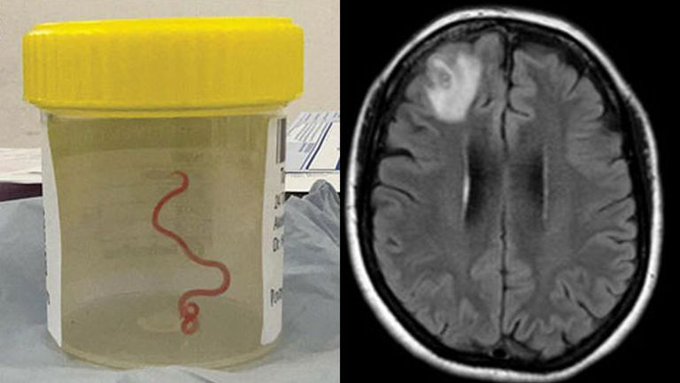

அவுஸ்திரேலிய பெண்ணொருவரின் மூளைக்குள் இருந்து உயிருடன் 8 சென்டிமீற்றர் புழுவை மீட்டுள்ளதாக விஞ்ஞானிகள் தெரிவித்துள்ளனர்.

மூளைக்குள் இருந்து உயிருடன் புழு மீட்கப்பட்டமை இதுவே முதல்தடவை என அவர்கள் தெரிவித்துள்ளனர்.

பெண்ணொருவர் வழமைக்கு மாறான வயிற்றுவலி இருமல் இரவுவியர்வை ஆகியவற்றால் பாதிக்கப்பட்டார்,அவருக்கு மனச்சோர்வு மறதிபோன்றவைகளும் காணப்பட்டன என தெரிவித்துள்ள வைத்தியர்கள் அந்த புழு இரண்டு மாதங்களாக அவரின் மூளைக்குள் இருந்திருக்கலாம் எனவும் தெரிவித்துள்ளனர்.

2021 பிற்பகுதியில் குறிப்பிட்ட பெண் மருத்துவமனையில் அனுமதிக்கப்பட்டார்,அவ்வேளை மேற்கொள்ளப்பட்ட ஸ்கானில் மூளையின் வலது மூளையில் வித்தியாசமான காயம் இருப்பது தெரியவந்தது.

நான் அதனை வெளியில் இழுத்தேன் அது அசையதொடங்கியது என புழுவை மூளைக்குள் கண்டுபிடித்த நரம்பியல் சிகிச்சை நிபுணர் தெரிவித்துள்ளார்.

ஸ்கானில் வித்தியாசமாக தென்பட்ட மூளையின் பகுதியை தொட்டபோது நான் அதனை உணர்ந்தேன் என அவர் தெரிவித்துள்ளார்.